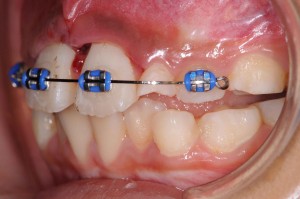

右上中切歯(右の真ん中の歯)は歯根破折、左上中切歯は歯牙脱臼を起こしていました。脱臼については、そこそこ固定できればどのような方法でもくっついてくれますが、歯根破折の場合は、処置によって大きく結果が異なります。

ポイントは「元あった位置にいかにピッタリ戻し、その位置で強固に固定できるか」ということです。この症例では、横の乳歯が一方はない、もう一方がぐらぐらしているということで固定源としては使えませんので、一つ飛ばして真ん中から3番目の乳歯にそれを求めなければなりません。

さらに固定した位置がずれないように、また、割れている部位に介在している一日経って弾力が出てしまった血餅をつぶしながらの固定ですから、大きな硬いワイヤーを曲げて使用しなければ目的を達することができない難しさもあります(血餅の排除に限度があったため、僅かな隙間は存在します)。

さらに固定した位置がずれないように、また、割れている部位に介在している一日経って弾力が出てしまった血餅をつぶしながらの固定ですから、大きな硬いワイヤーを曲げて使用しなければ目的を達することができない難しさもあります(血餅の排除に限度があったため、僅かな隙間は存在します)。